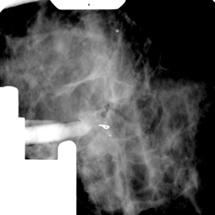

Die Lage des Befundes wird durch Mammografie-Aufnahmen aus unterschiedlichen Winkeln bestimmt. Dabei wird nur ein kleiner Anteil der Brust von 5 x 5cm Größe geröntgt. So kann mittels eines Computers die Lage des Befundes exakt bestimmt werden.